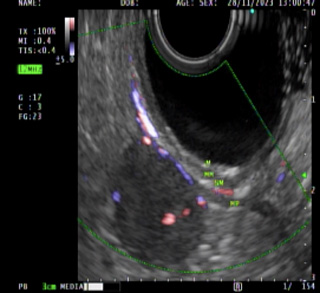

Imagen 2.Tumor gástrico dependiente de la capa muscular. |